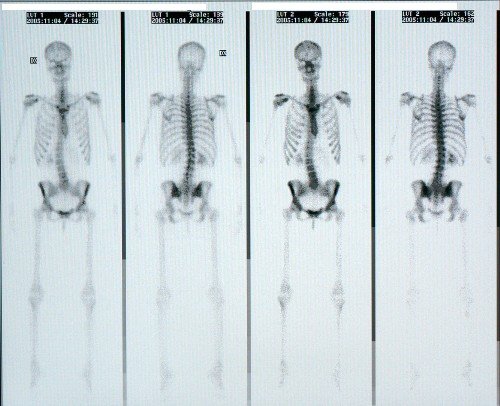

Just nu är jag föräldraledig, men annars arbetar jag som biomedicinsk analytiker inom klinisk fysiologi, och framförallt nuklearmedicin. Enkelt förklarat så undersöker jag olika organ i kroppens funktion för att läkare sedan ska kunna ställa en diagnos. Ett radioaktivt ämne injiceras, tar sig till organet som ska undersökas och vi tar bilder med gammakameror som fångar upp strålningen som kommer från kroppen.